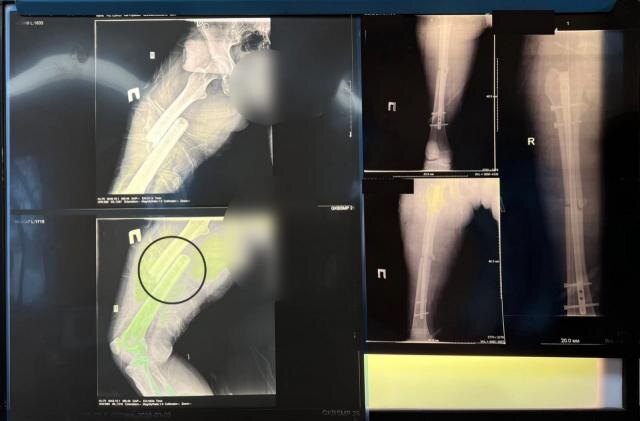

Как пояснили РИАЦ в облздраве, у пациентки была диагностирована сочетанная травма, которая включала в себя закрытую ЧМТ, открытый перелом средней трети бедренной кости со смещением и перелом вертлужной впадины (тазовых костей). Серьёзное повреждение опорно-двигательного аппарата сопровождалось обильным кровотечением из отломков костей и мягких тканей. При переломе бедренной кости девушка потеряла около 1,5 литров крови, что могло привести к травматическому шоку. В случае открытого перелома риск для жизни значительно возрастал.

«При поступлении было обнаружено, что отломки бедренной кости заходят друг за друга более чем на 11 сантиметров. Мы настроили систему скелетного вытяжения. Через несколько дней на контрольном рентгене мы увидели, что захождение практически устранено благодаря поэтапному увеличению груза на скелетном вытяжении, - рассказал лечащий врач пациентки Пётр Ершов.

После заживления ран на бедре пациентка была готова к операции, которую провели специальным методом, позволяющим минимизировать кровопотерю. Вмешательство выполнялось через небольшие разрезы с введением штифта внутрь кости, который блокируется специальными винтами. Благодаря успешному применению системы скелетного вытяжения медики смогли избежать излишней травматизации пациентки во время операции.